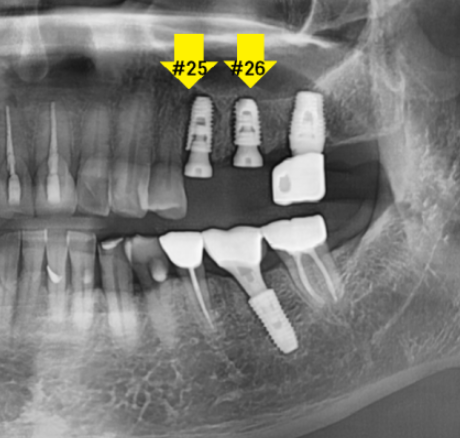

파노라마 전체 사진상으로도

좋아 보이지 않아

자세히 관찰할 수 있는

작은 x-ray를 한 장 더 찍어 보았습니다.

노랗게 동그라미 친 부분이

치아 뿌리 끝에 염증을 의미합니다.

이미 치료를 받은 치아에 염증이 생겨

주변 뼈를 녹이고 있는 상태

옆에 치아도 좋지 않은 것은 마찬가지였습니다.